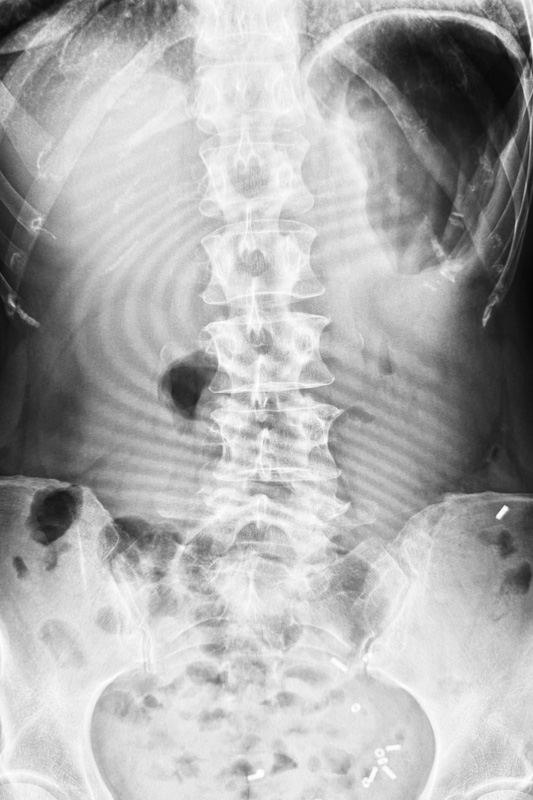

Das moderne Röntgen steht für eine exzellente Darstellung und Beurteilung von Erkrankungen z.B. im Bereich des Brustkorbs und Bauches oder auch bei Verletzungen des Skelettsystems.